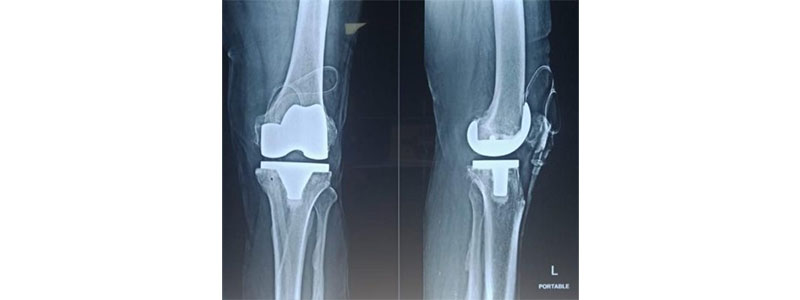

Knee Replacement medical procedure is a methodology that includes supplanting a harmed knee joint with a fake embed. During the activity metallic embed assists with easing agony and great scope of movement across the joint.

Knee replacement is where bits of the bones that structure the knee joint are taken out and supplanted with counterfeit inserts. It is performed essentially to assuage knee agony and solidness brought about by osteoarthritis.

• Complete knee replacement, where the whole joint is supplanted with fake surfaces

According to Knee Replacement Doctor in Thane, Knee replacement medical procedure requires about one hour and includes eliminating the harmed ligament and bone from the joint and supplanting them with counterfeit metallic inserts. These inserts can be set in various pieces of the knee: the lower end of the femur (metal cobalt-chronium or Titanium piece), the upper finish of the tibia ( metal cobalt-chronium/titanium piece), or at the rear of the kneecap (made areas of strength for of).